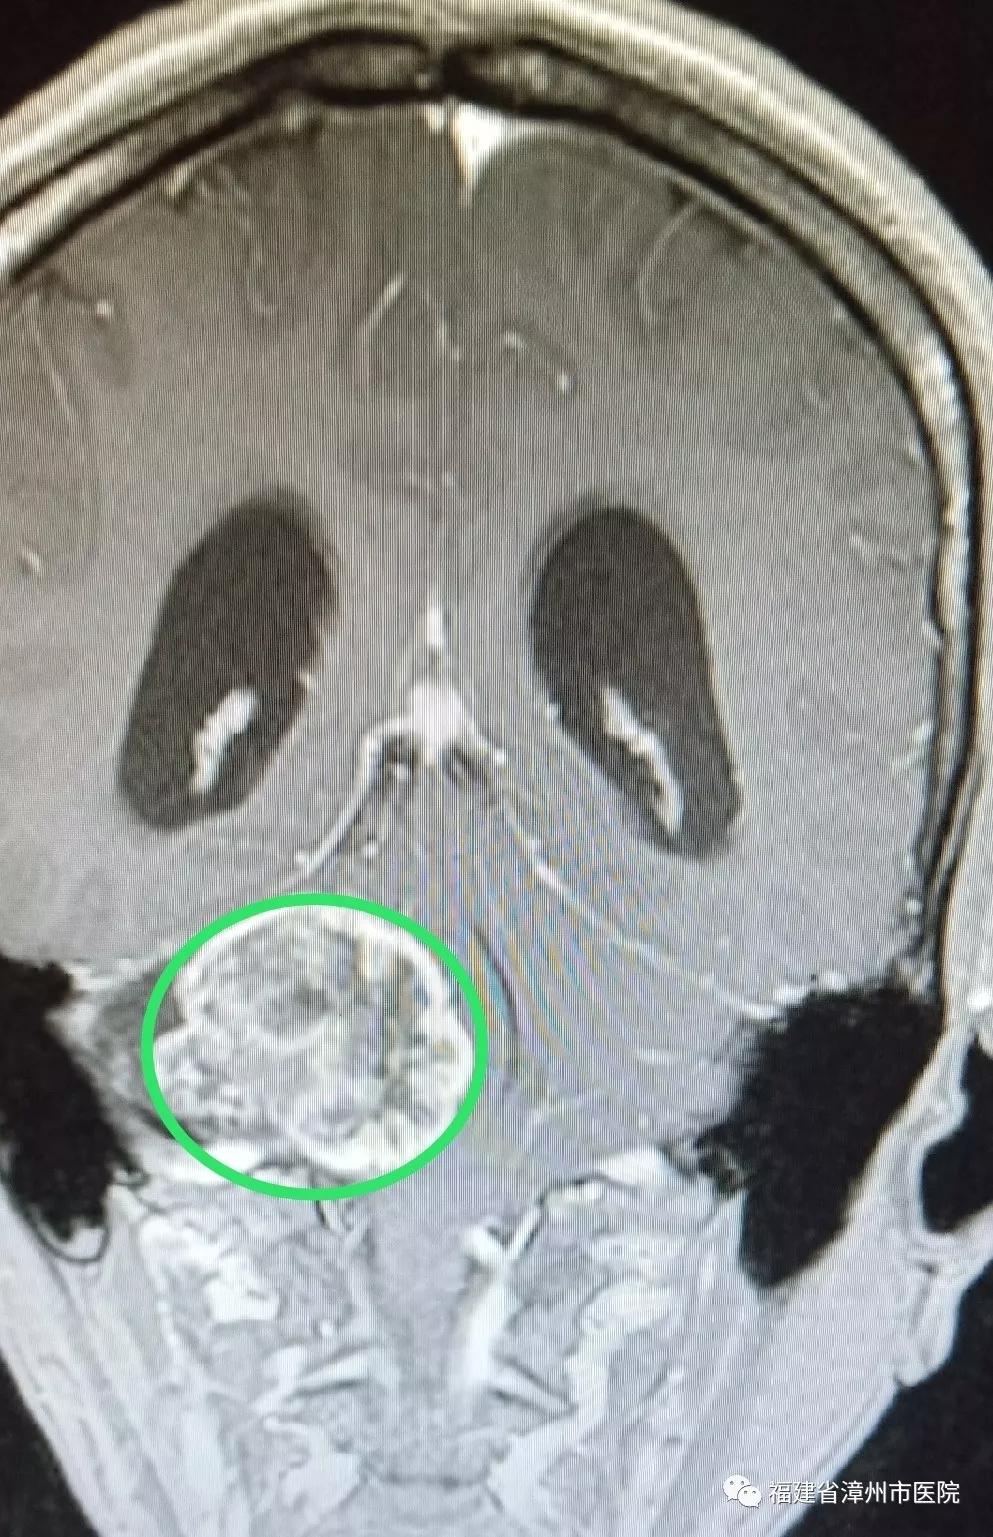

术前(肿瘤)